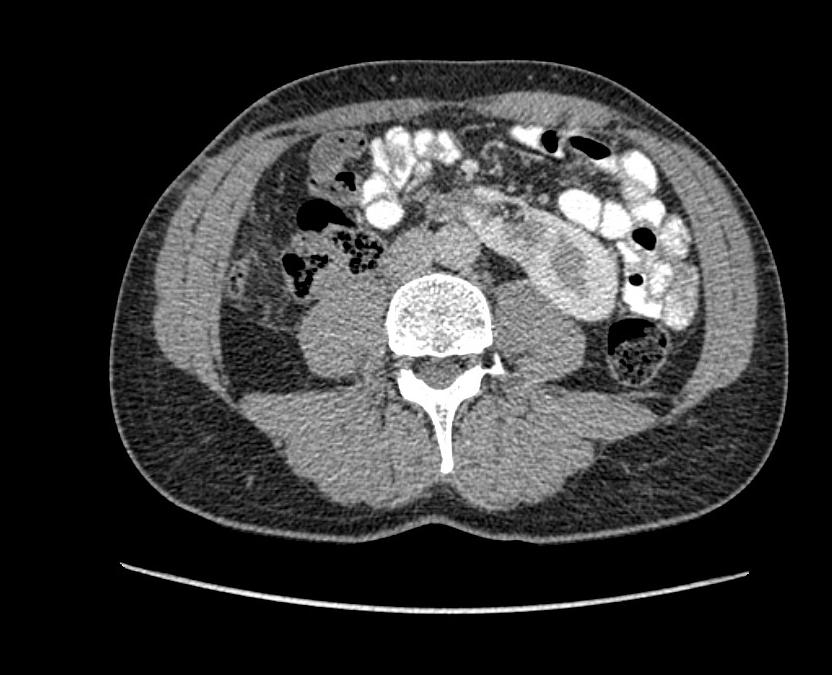

Obr. 1. Perioperační CT snímek během MWA.

Fig. 1. Perioperative CT scan during microwave ablation.

Výkon byl prováděn mikrovlnným systémem Solero Microwave Tissue Ablation System (AngioDynamics, Inc., USA). Během ablačních výkonů byla používána frekvence 2,45 GHz a výkon v rozsahu 100–140 W. Jako aplikátor byla používána nerezová ocelová jehla s keramickým hrotem o průměru 15 G a délce 14, 19 nebo 29 cm. Jedna ablační sekvence po zavedení jehly do tumoru trvá 4–6 min podle velikosti nádoru, v průběhu jednoho výkonu jsou standardně prováděny 1–2 ablační sekvence. Maximální velikost ablační zóny udávaná výrobcem je 54 × 39 mm na jednu sekvenci. Po skončení ablace tumoru se během vytahování jehly provádí ablace-koagulace punkčního kanálu (track ablace). Výkon je prováděn v analgosedaci za přítomnosti anesteziologa, pacienti snášejí výkon dobře. Celková doba výkonu vč. polohování pacienta a přípravy CT pracoviště je 60–90 min (obr. 1).